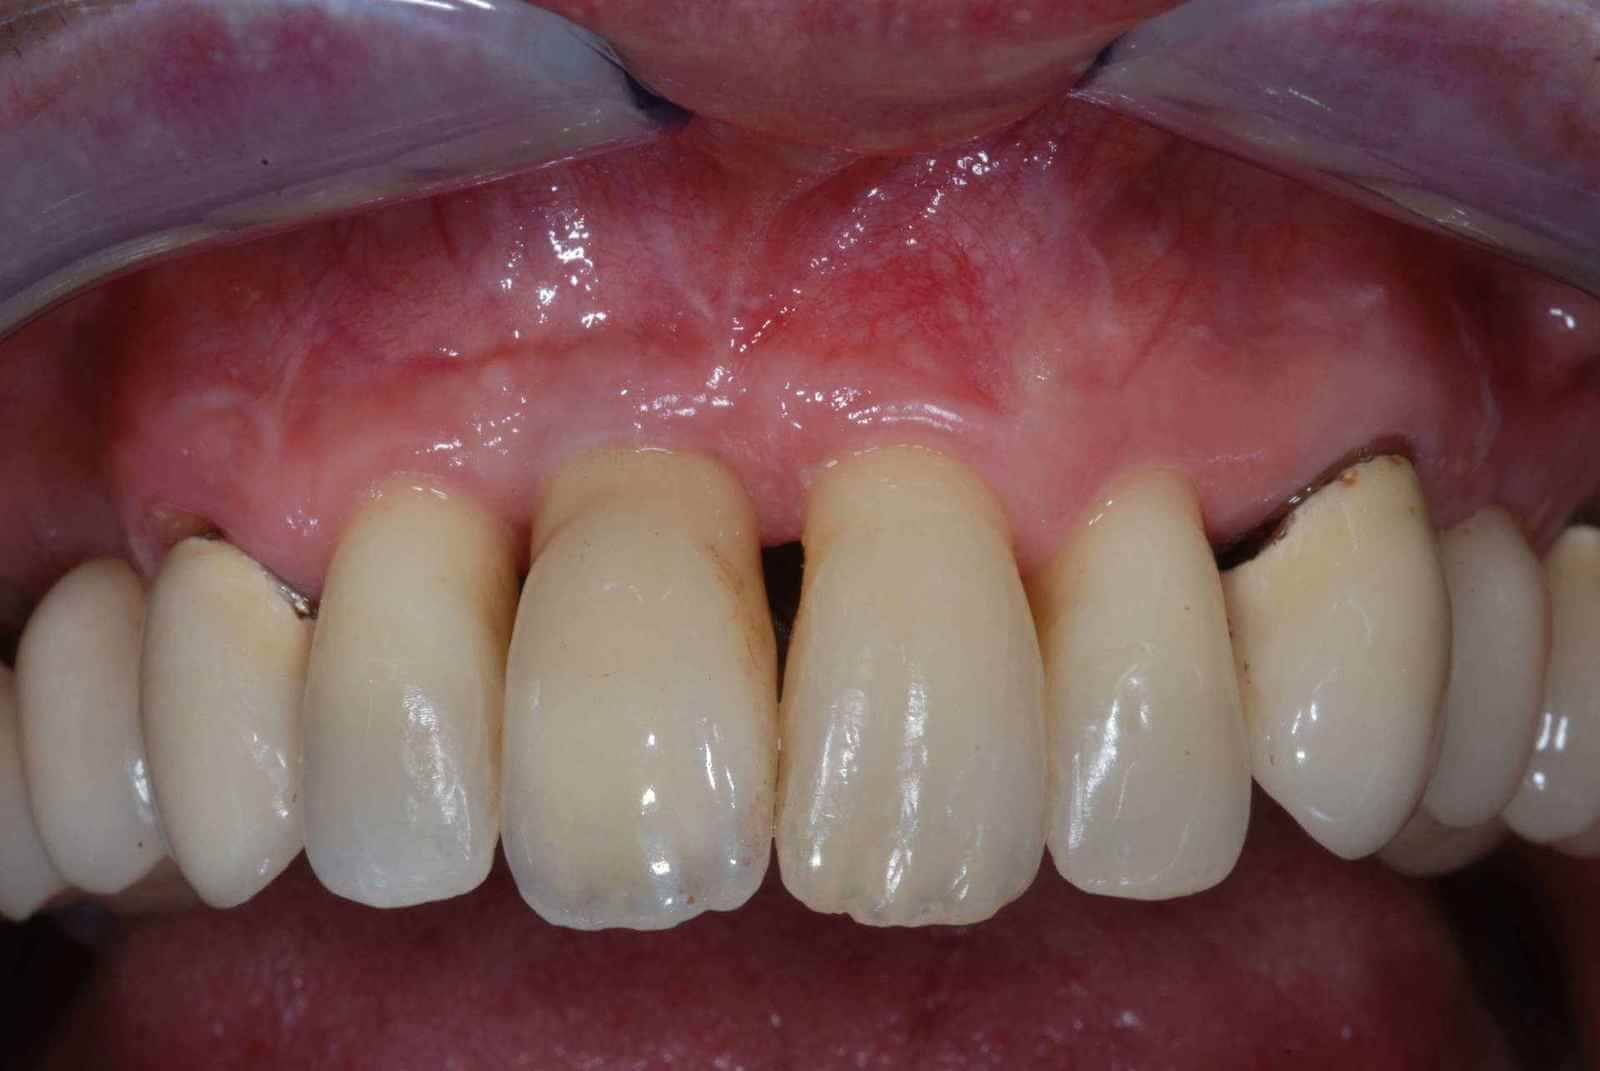

Mi occupo di parodontologia da decenni. E' la branca dell'odontoiatria che cura i tessuti di sostegno del dente. Se hai gengive infiammate, gonfie, che sanguinano durante l'uso dello spazzolino, se hai recessioni gengivali, sensibilità al freddo o alitosi, potresti avere la parodontite. Più aspetti, più perdi osso di sostegno fino a quando i tuoi denti si muoveranno fino a farti male durante la masticazione e saranno da estrarre. Affidati alle cure di un parodontologo, prima che sia troppo tardi.